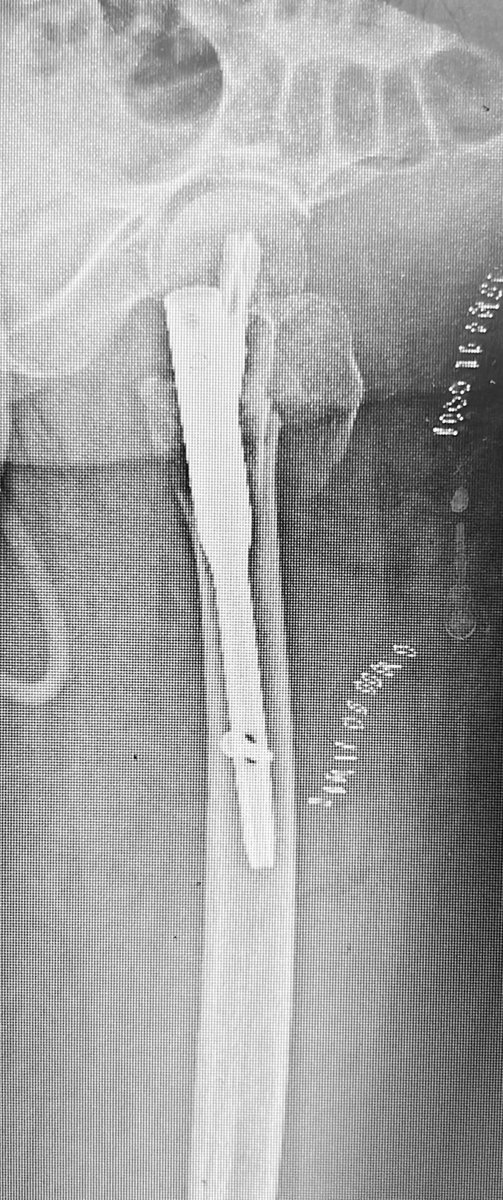

77 yo, pluripathological patient, combo nail and plate. Suprapatellar nail